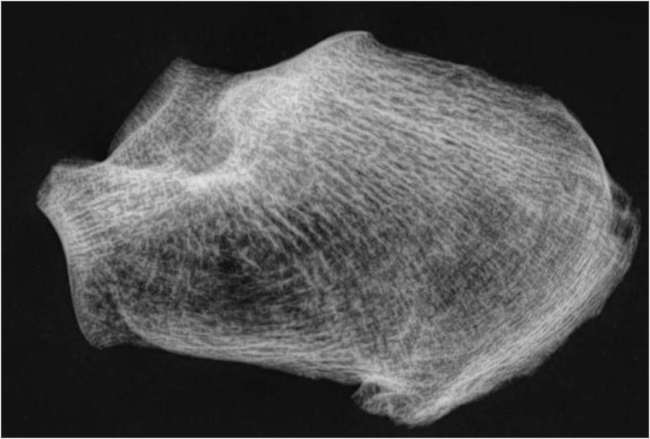

Fase III (borderline): Se observa una disminución del grupo primario tensil, el cual sólo se cruza con el pilar inferior del grupo compresivo primario (►Fig. 3).